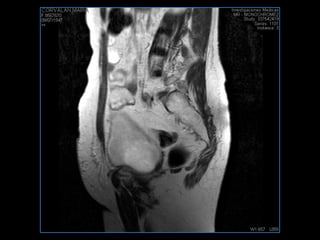

PROTOCOLO pelvis SAG T2, Y FAT SAT (FINOS) AXIAL T1  AX FAT SAT CON   GADOLINIO :  AX T1 Y COR T1 SAT: NO  FASE: RL THK: 3MM  COIL:  GAP: (FACTOR 1.4) 1MM FOV: 40 CM NEX:2 SINCRONIZACION RESPIRATORIA EN 3 O 4 CICLOS ALE

resonancia de abdomen